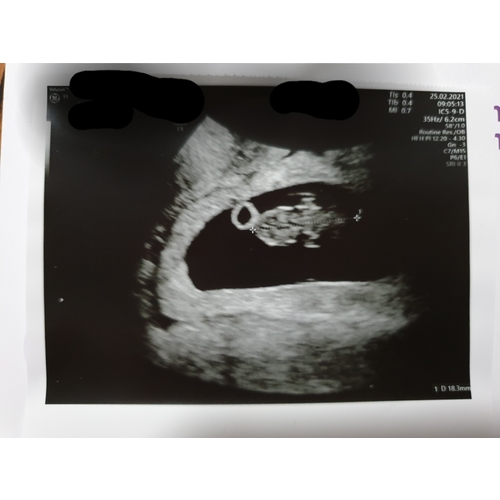

Dit is dan het model voor een uitwendige echo ! Inwendig is het andersom

Oke dan ben ik heel erg benieuwd wat dit dan eventueel kan zijn volgens de ramzi methode dit is een inwendige echo geweest bij 8 weken zwangerschap

Inwendige echo: Zie je op de uitdraai van een inwendige echo de lichte vlek rechts in de baarmoeder? Dan verwacht je volgens de Ramzi-theorie een jongen. Wanneer je hem links in de baarmoeder ziet, zou je van een meisje in verwachting zijn.

Uitwendige echo: Als de echo via je buik is gemaakt, is de echo gespiegeld. Zie je op de uitdraai van de echo de lichte vlek rechts? Dan zou dit betekenen dat je een meisje krijgt. Een lichte vlek aan de linkerkant wijst bij een uitwendige echo op een jongen.

Bij mij is de echo uitwendig gemaakt. Was toen precies 8 weken. Zoals ik he ...